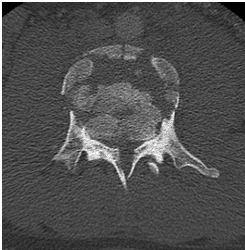

18 yo fell from 3 floors. Near complete loss of all neurological functions below the level of injury with near complete involvement of bowel and bladder

Patient was operated and the spinal canal cleaned up of all bony fragments. The spine was fixed from the side and the back to take care of instability.